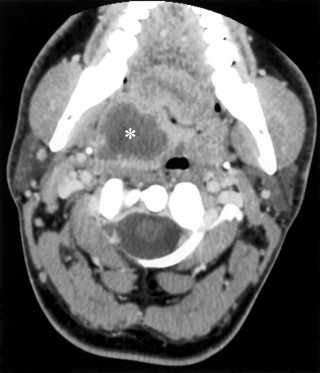

扁桃周囲膿瘍

造影CTで、周囲に造影効果のある低吸収域として描出される (*)。口腔咽頭と舌は変位している。

出典

1: Flint PW, Haughey BH, Robbins KT, et al. Cummings Otolaryngology: Head & Neck Surgery, 5th ed. Elsevier, 2010; Figure 102-31.